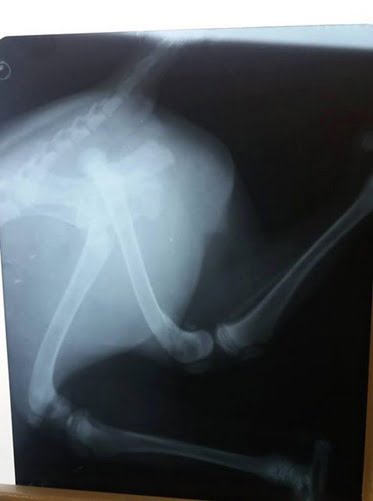

В один день (в субботу, 06.10.2018) в Корабельном районе на проезжей дороге были сбиты 2 собаки: 3-месячный щенок и старая собака.

фото щенка, сделанное Анной буквально за минуты до аварии и после

«В обоих случаях ни один водитель не остановился, чтобы помочь животным, которые остались лежать на дороге!!! Только благодаря зоозащитникам и нескольким небезразличным жителям района у собак есть шанс на ЖИЗНЬ! У них переломы, ЧМТ, лечение только за свой счет и благотворительные перечисления», — рассказала женщина.